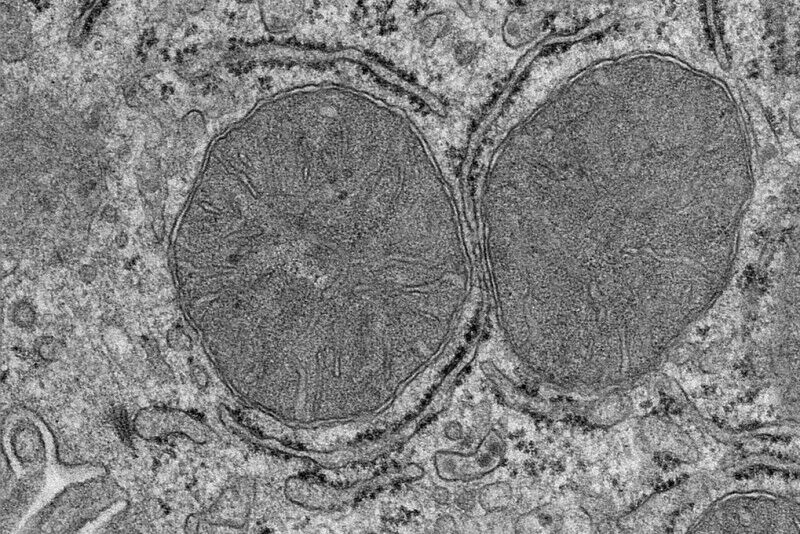

What happens in the body when we are hungry and see and smell food? A team of researchers at the Max Planck Institute for Metabolism Research has now been able to show in mice that adaptations in the liver mitochondria take place after only a few minutes. Stimulated by the activation of a group of nerve cells in the brain, the mitochondria of the liver cells change and prepare the liver for the adaptation of the sugar metabolism. The findings could open up new avenues for the treatment of type 2 diabetes.

The researchers fed hungry mice that could only see and smell the food without eating it. After just a few minutes, the researchers analysed the mitochondria in the liver and found that processes normally stimulated by food intake were activated.

The studies show that it is sufficient for the mice to see and smell food for a few minutes to influence the mitochondria in the liver cells. This is mediated by a previously uncharacterised phosphorylation in a mitochondrial protein. Phosphorylation is an important modification for the regulation of protein activity. The researchers also show that this phosphorylation affects the sensitivity of the liver to insulin. The researchers have thus discovered a new signalling pathway that regulates insulin sensitivity in the body.

"When our senses detect food, our body prepares for food intake by producing saliva and digestive acid. We knew from previous studies that the liver also prepares for food intake. Now we have taken a closer look at the mitochondria in liver cells, because they are essential cell organelles for metabolism and energy production, and realised how surprisingly fast this adaptation takes place," explains Sinika Henschke, first author of the study.